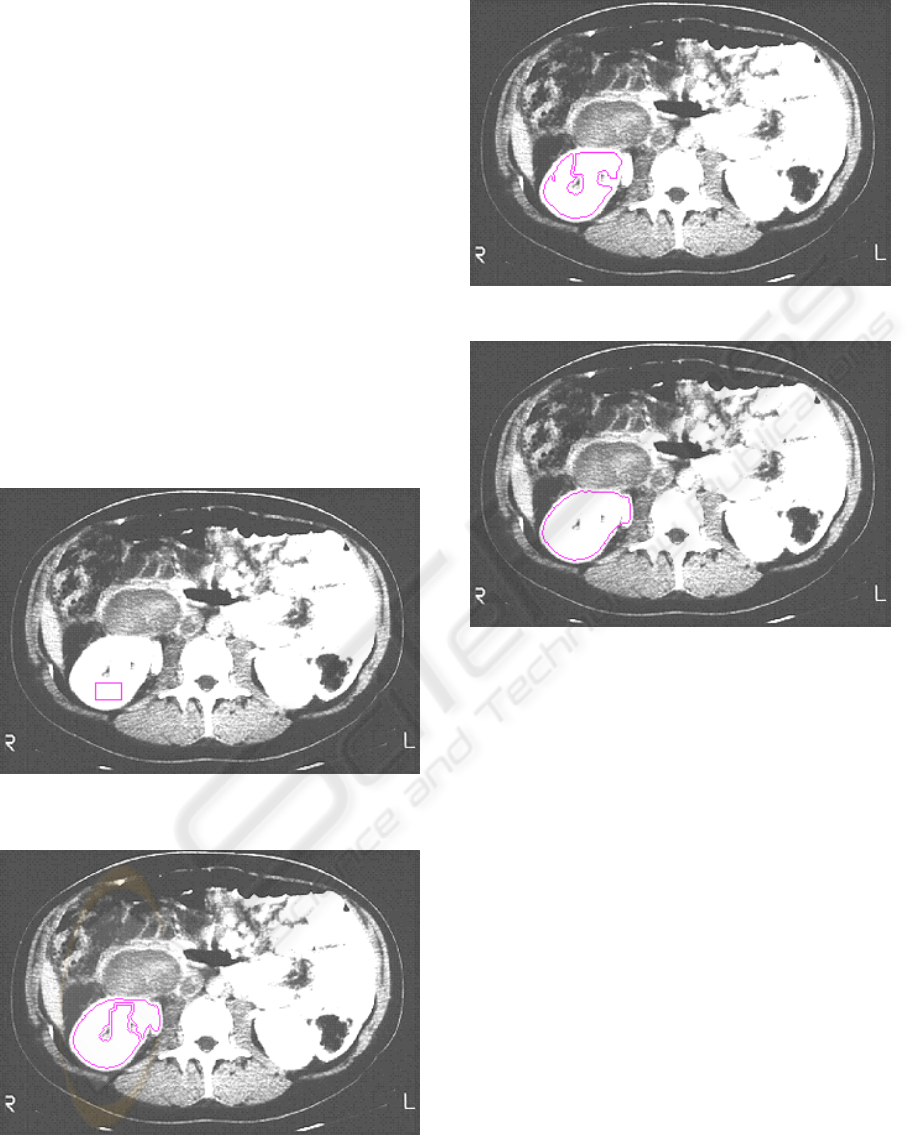

Figure 1: Evolution of a closed curve C represented by a

function Φ between time intervals t and t+∆t.